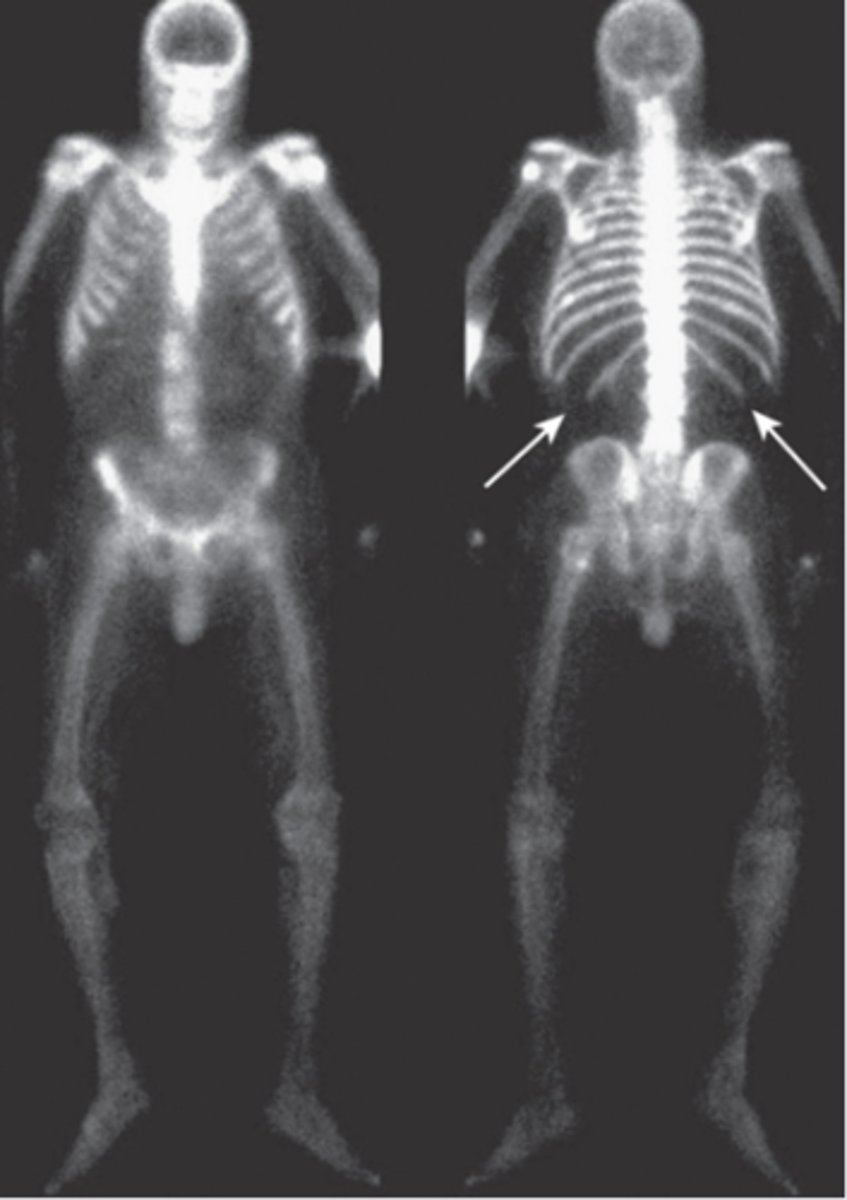

Nuclear medicine bone scan- study of choice for detecting skeletal metastases

radionuclide bone scan

metastatic disease involving nearly every bone in the axial skeleton

focal disorder of bone metabolism, accelerated bone remodeling resulting in overgrowth, impairs integrity of affected bone, X-Ray and radionuclide bone scan